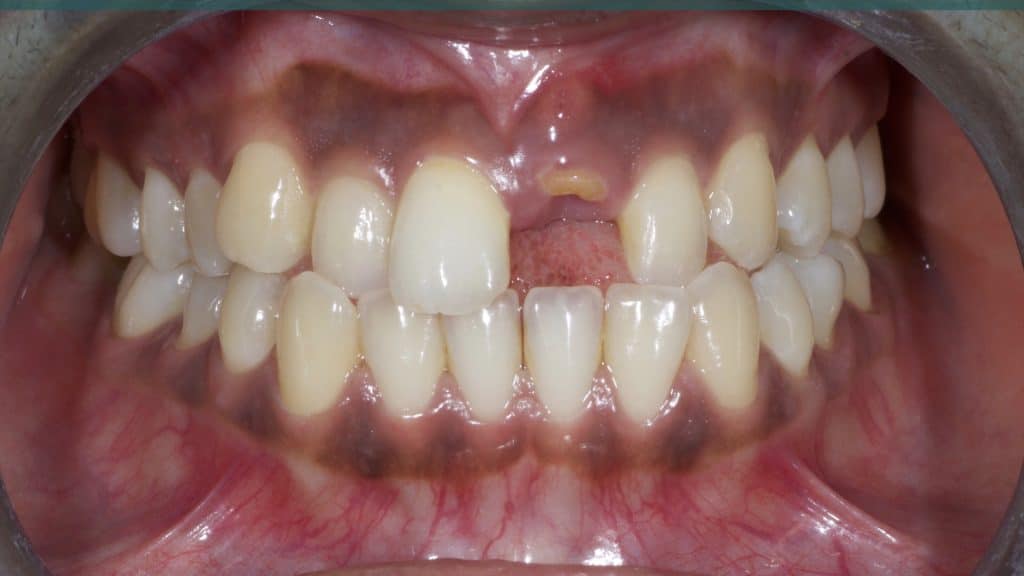

20 days post-op after suture removal